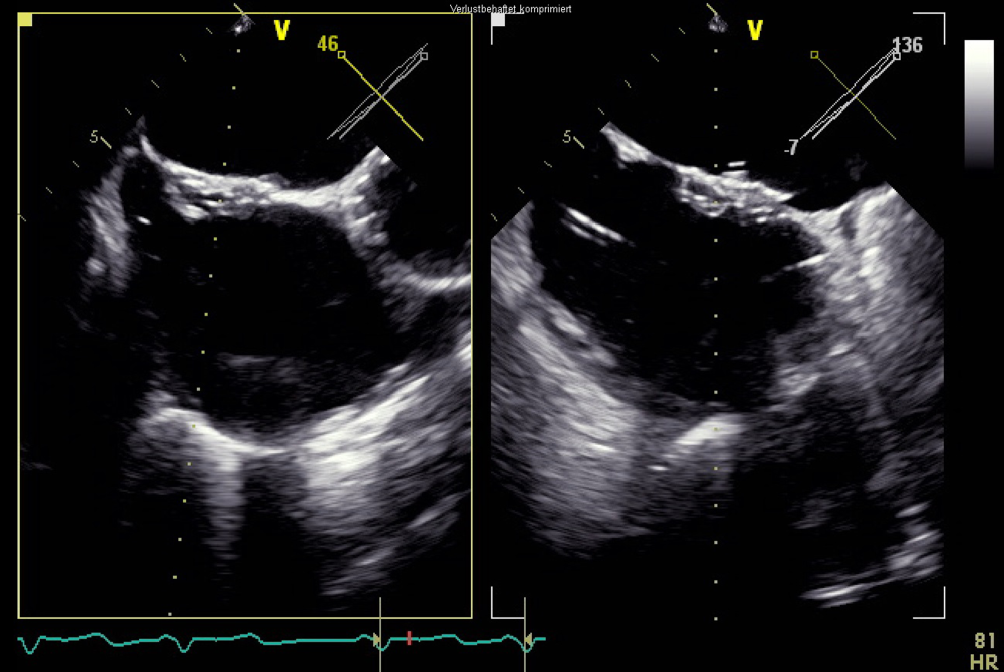

In der transösophagealen Echokardiographie zeigte sich eine deutlich exzentrische, hochgradige Mitralklappeninsuffizienz aufgrund eines partiellen Sehnenfadenabrisses im Segment P2 mit einem nach posterior gerichteten Jet (Abb. 1 und 2). Des Weiteren zeigten sich eine gute systolische linksventrikuläre Funktion und kein Hinweis auf einen Shunt auf Vorhofebene. Eine echokardiographische Abklärung des rechten Ventrikels ergab eine visuell leicht reduzierte Funktion bei einer reduzierten Anulusgeschwindigkeit von 7 cm/s, jedoch noch erhaltener longitudinaler rechtsventrikulärer Funktion („tricuspid annular plane systolic excursion“ 2 cm). Des Weiteren wurde eine mittelgradige Trikuspidalklappeninsuffizienz bei Anulusdilatation festgestellt.

Abb. 1

Transösophageale Echokardiographie. 3‑D-Ansicht mit Aufsicht auf die Mitralklappe. Zu sehen ist der Sehnenfadenabriss im Segment P2

Abb. 2

Transösophageale Echokardiographie. 2‑D-Ansicht im 3‑Kammer-Blick auf die Mitralklappeninsuffizienz mit nach posterior gerichtetem Jet